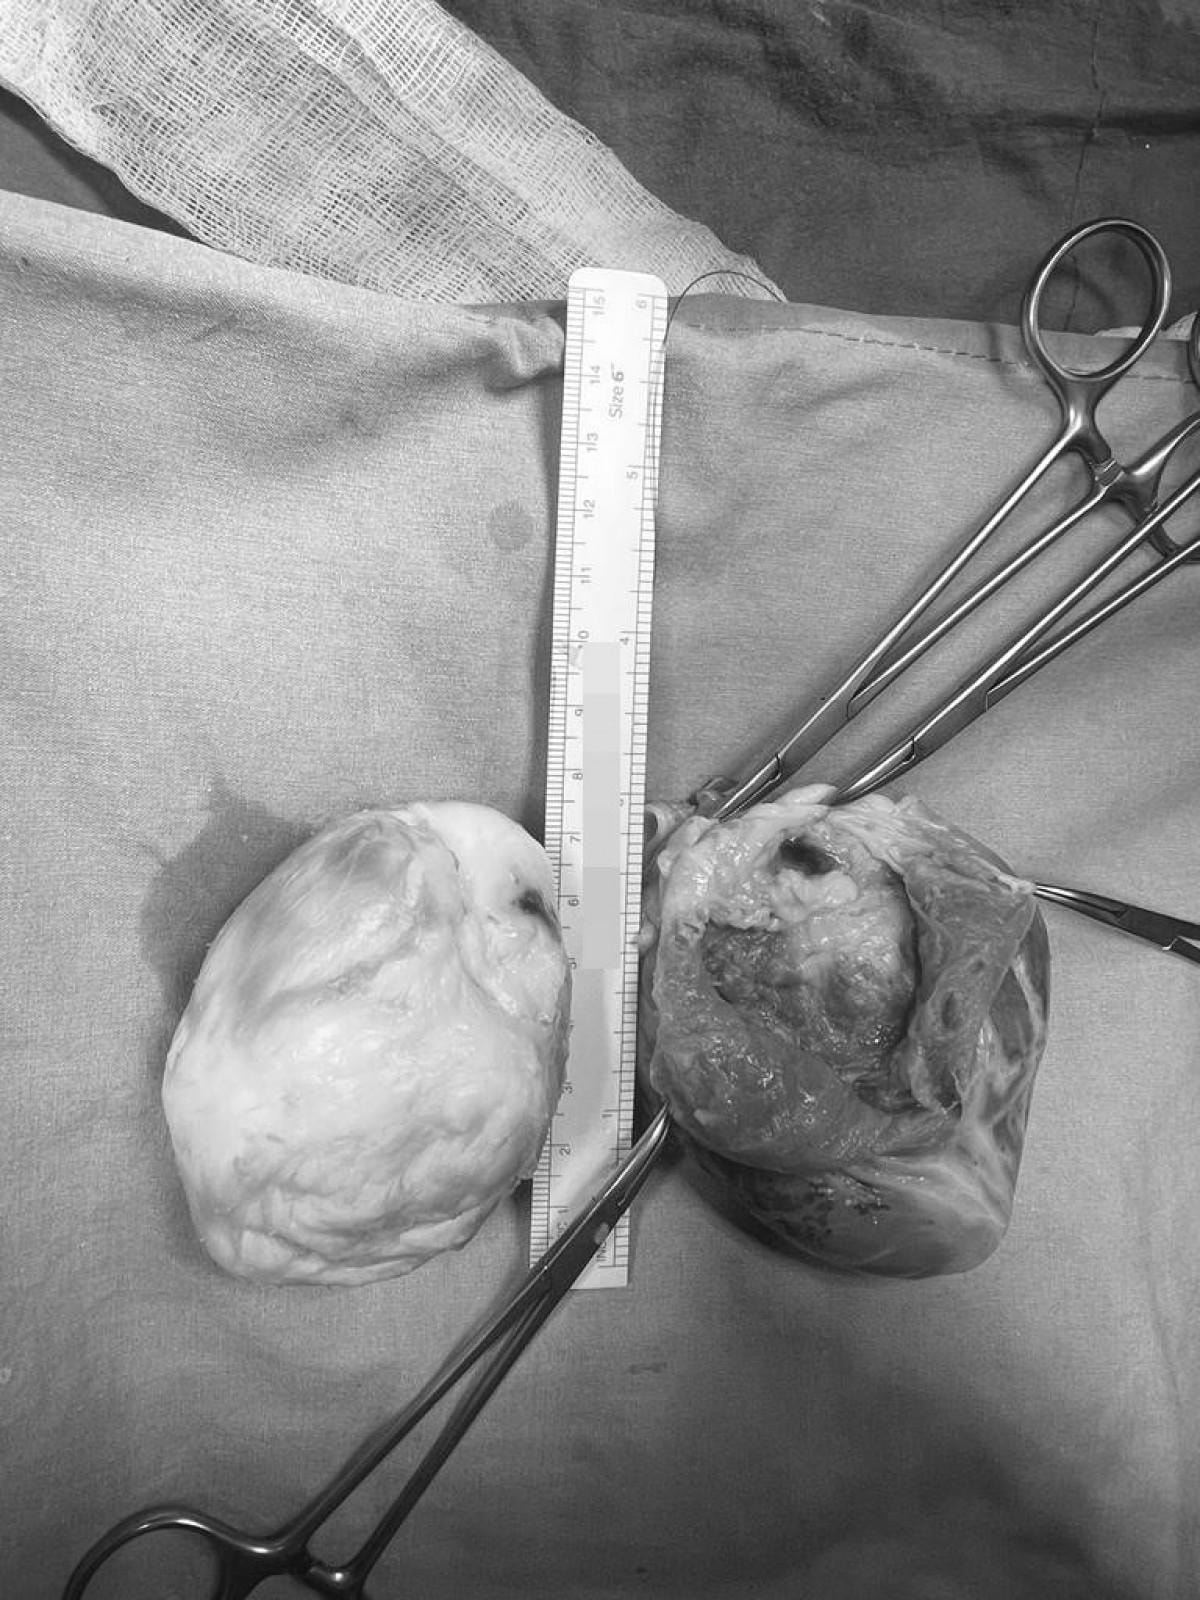

Ekin Ada kızımızla 32 haftada anne karnındayken ilk olarak tanıştım. Fetal EKO'sunda bir kalp tümörü tespit edilmişti. Kızımız doğdu, ondan sonra 3 ila 6 aylık aralarla izlemeye başladık. Kalp içindeki tümör yaşı büyüdükçe, kalple beraber büyüyordu. Bu tümörlerin bir kötü tarafı da ritim düzensizlikleri yaratmaları. Ani ölüm riskinin çok yüksek olduğu vakalar bunlar. Tümörün büyüklüğü neredeyse kalp kadar olmuştu. 7 santimlik bir tümör, Ekin Ada'nın kalbi 8 santim uzunluğundaydı zaten. Sol karıncıktaki tümörün bir büyük tehlikesi daha vardı. Önemli bir koroner arter damar, tümörün içinden geçiyordu.

Çok dikkatli çalışmamız gerekiyordu o nedenle kalbi yerinden söktük, damarlarından ayırdık ve masanın üzerine yatırarak (kalp vücuttan ayrıyken) ameliyata devam ettik. Göğüs boşluğu tamamıyla boş kaldı, 'kalpsiz' bir durumda makineye bağlı takip edildi. Kalbi masanın üzerinde sol karıncığa hasar vermeden, hem kasları hem arterleri koruyarak açtık. Dr. Yılmaz Zorman ile beraber nefesimizi tuttuk, ince ince, soğan kabuğu soyar gibi kalp kasından tümörü ayırdık. Tümörün içinden geçen o ince, bir milimetrelik koroner damarı bulduk ve onu da titiz bir şekilde tümörden ayırarak kalbi tamamen temizledik. Onarılmış kalbi tekrar yerine taktık.